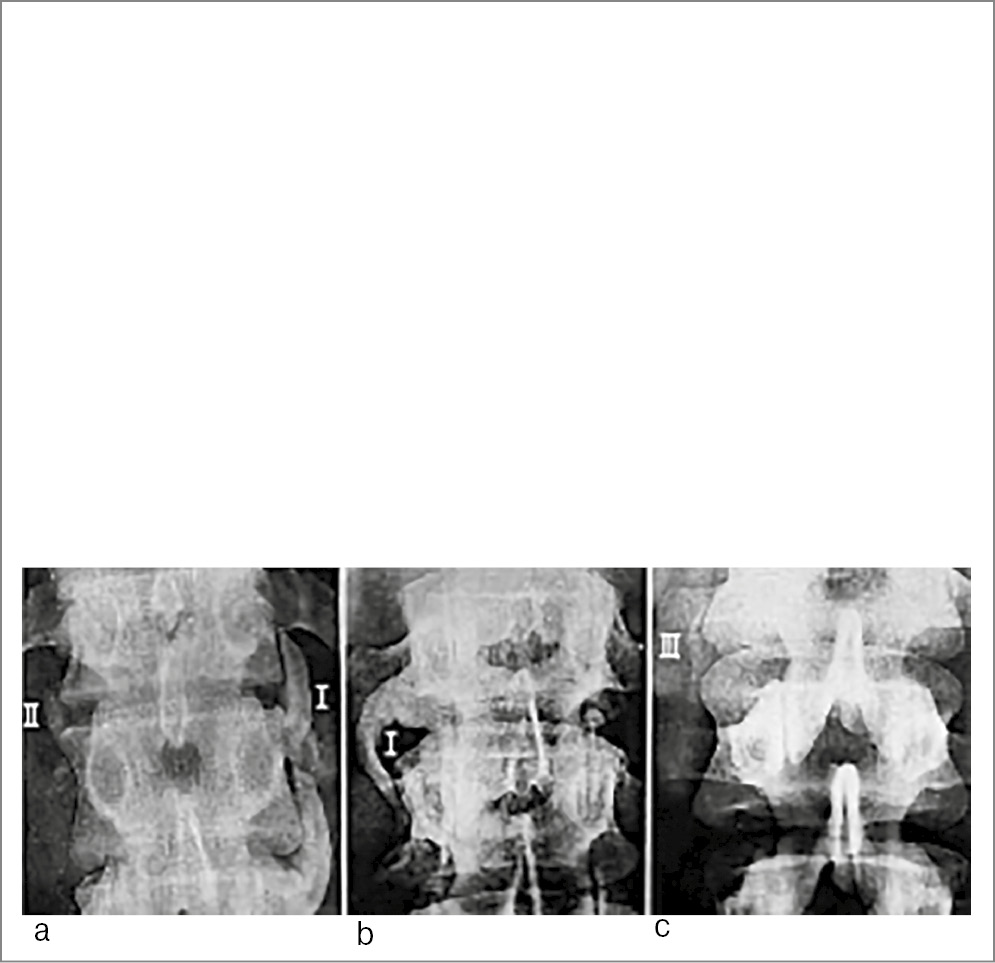

На рентгенограммах позвоночника при идиопатическом АС, но чаще у пациентов с ПсСп можно наблюдать парасиндесмофиты. В отличие от синдесмофитов приведенные оссификаты либо не соединяются с позвонками, либо контактируют только с одним позвонком, образуя неполные костные «мостики», несмыкающиеся «скобки», причем если парасиндесмофит и соединяется с телом позвонка, то не на уровне его угла, а отступив от него. Иногда они по форме напоминают рог быка или перевернутую запятую. Морфогенез парасиндесмофитов не изучен. Предположительно, эктопической оссификации подвергаются в данных случаях отрезки коротких передних продольных связок позвоночника или недифференцированная соединительная ткань, расположенная между телом позвонка и этими связками. Парасиндесмофиты немногочисленны, несимметричны, развиваются почти исключительно в поясничном отделе и намного реже в шейном отделе. Со временем их число обычно не увеличивается. Термин «парасиндесмофит» предложен немецким радиологом W. Dihlmann в 1968 г. [6]. Фотография из его книги, иллюстрирующая 3 типа парасиндесмофитов, приведена на рис. 6.

Рис. 6. Рентгенограммы позвоночника разных пациентов. Парасиндесмофит типа I направлен краниально (a) или каудально (b), слегка изогнут, может касаться соседнего позвонка, но не срастается с ним, напоминает по форме рог быка. Парасиндесмофит типа II (a) расположен на уровне межпозвонкового промежутка, короткий, имеет ровные контуры, не контактирует с телами позвонков (похож на вставочную косточку). Для парасиндесмофита типа III (c) также характерно отсутствие контакта с телами позвонков; он имеет неправильную удлиненную форму и расположен не только на уровне промежутка, но и вдоль соседних тел позвонков [Источник: Dihlmann W. Diagnostic radiology of the sacroliac joints. Georg Thieme Verlag Stuttgart, NY. 1980].

W. Dihlmann считал, что паравертебральные оссификаты характерны для ПсСП и реактивных артритов (РеА), но могут также наблюдаться при дегенеративных заболеваниях позвоночника или после травм. Подробный анализ различных видов паравертебральной оссификации показал, что при идиопатическом АС и при неспецифическом язвенном колите почти исключительно наблюдаются краевые (дисковые) синдесмофиты, а парасиндесмофиты крайне редки, хотя и возможны. У пациентов же с псориазом и РеА могут отмечаться как парасиндесмофиты, так и синдесмофиты (краевые и внедисковые) [7].